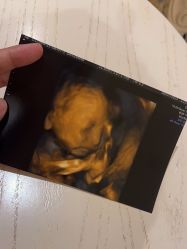

• 北京俪婴妇产医院(朝阳大悦城店)

• -北京俪婴妇产医院(朝阳大悦城店)

匿名用户 上传于 23-08-23 | 报错

匿名用户 上传于 23-08-21 | 报错